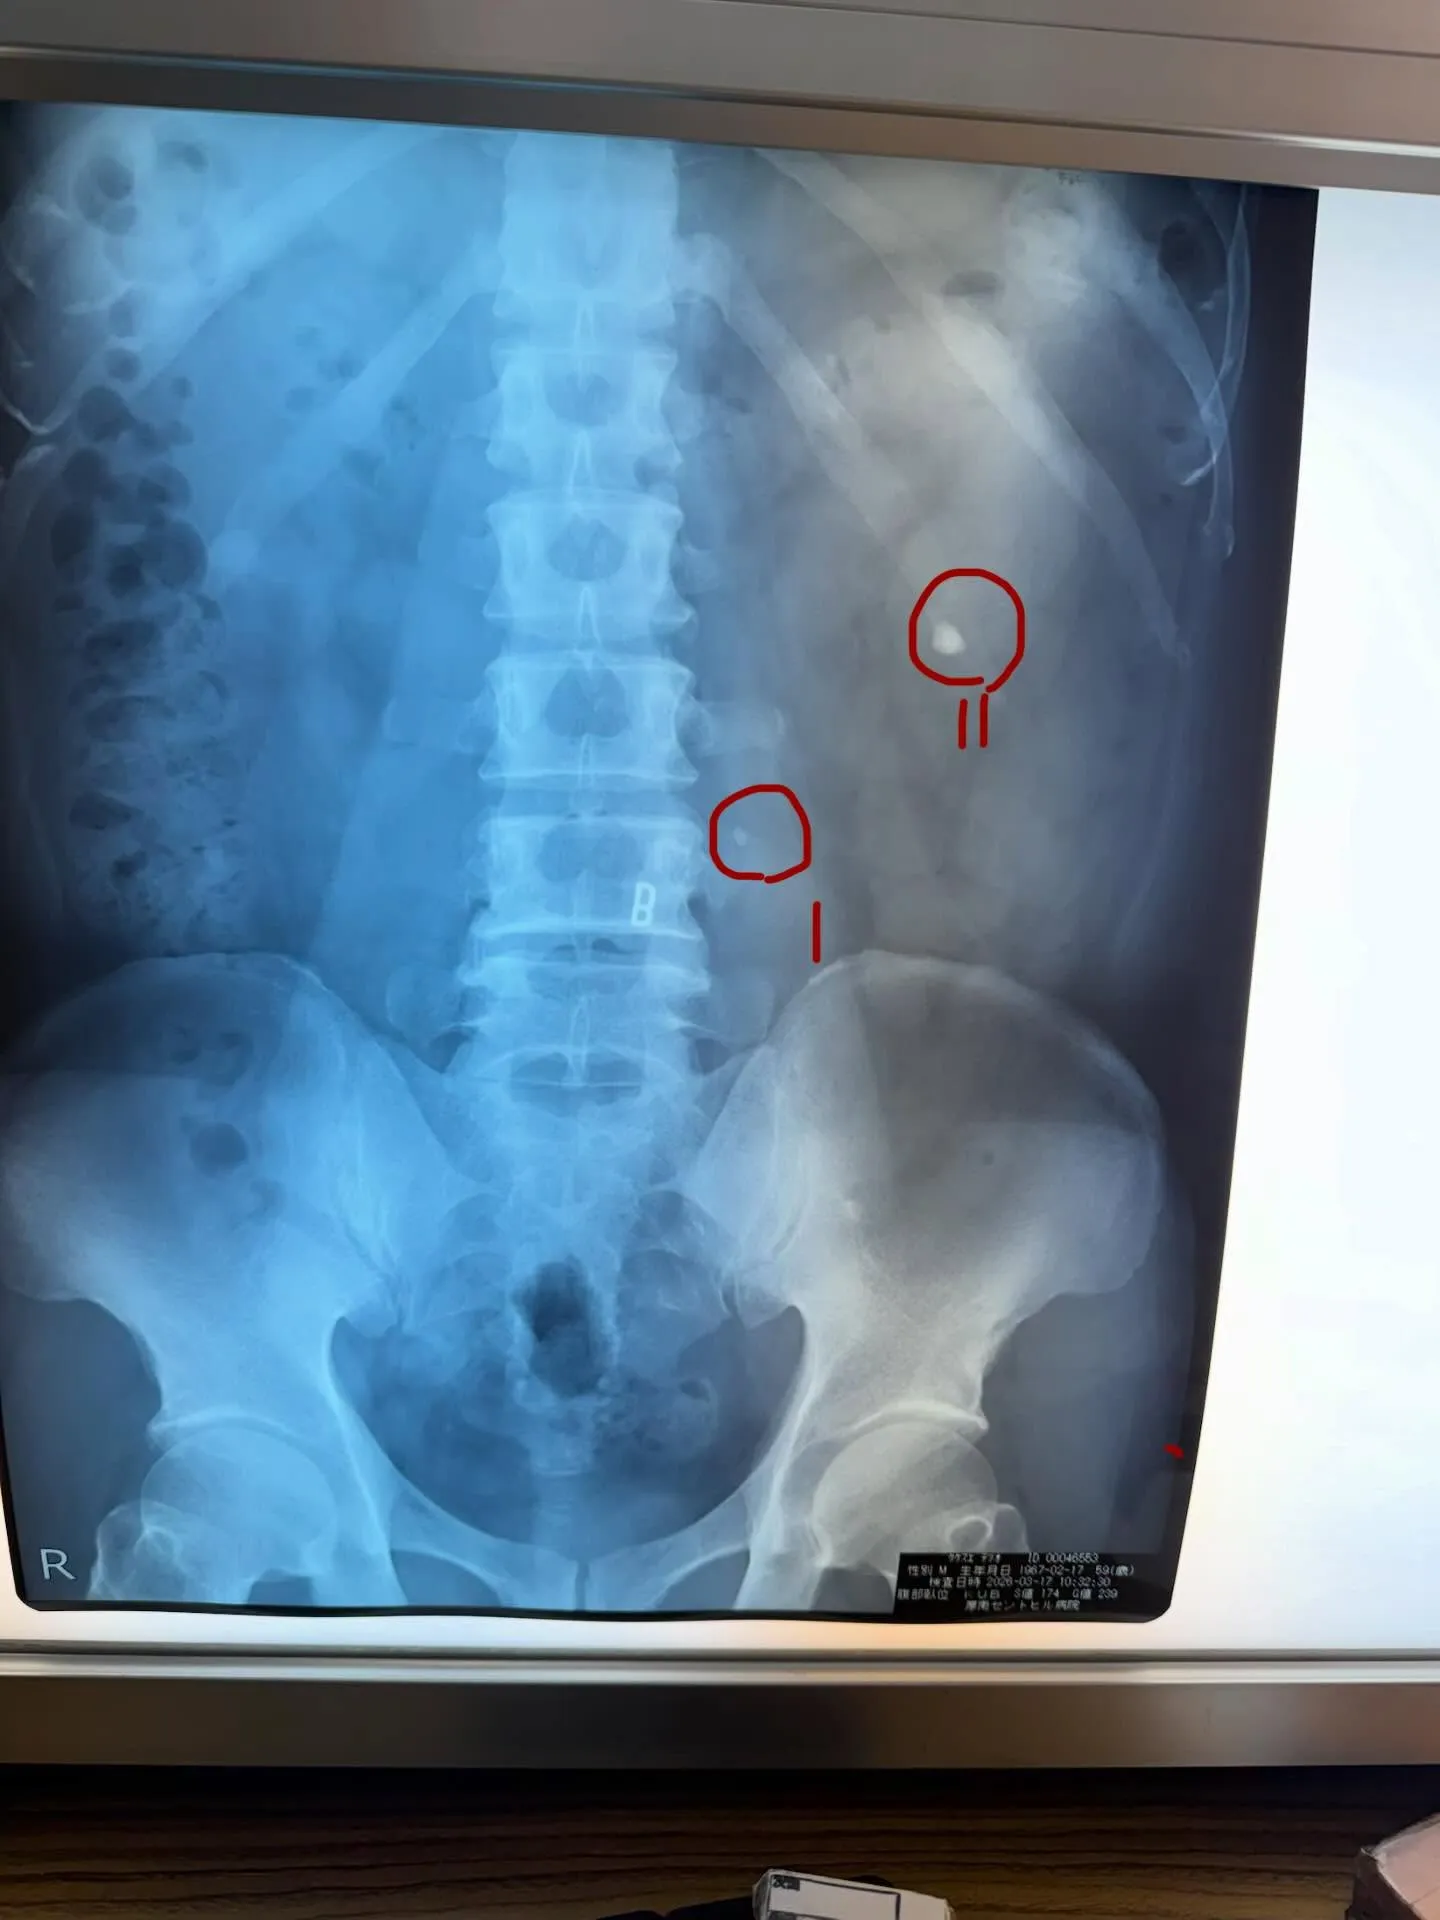

発見された結石は二つ

Ⅰ 痛みの原因、5㍉🪨 尿管を塞ぎ腎臓が腫れている模様

II 腎臓内に成長した石🪨今は悪さはしていない様子

いつかは砕く必要あり

の診断で明後日5㍉の石🪨を砕く事に